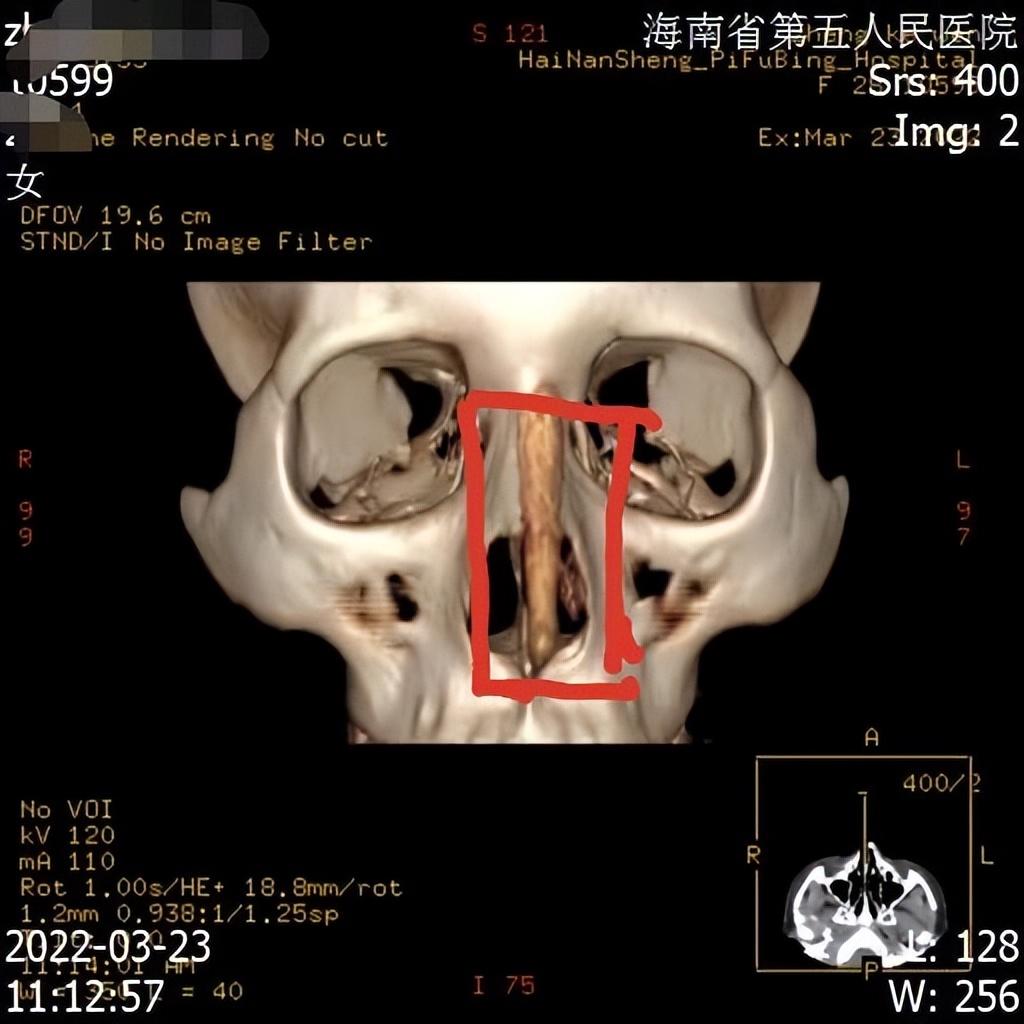

鄭女士在整完后,身邊人提醒她,鼻子怎么變歪了,她對(duì)著鏡子細(xì)細(xì)端詳,感覺鼻子確實(shí)被整歪了,為了證實(shí)不是眼神和角度問題,她便去海南省第五人民醫(yī)院拍片。“人的主觀視覺可能會(huì)看走眼,但機(jī)器固定拍攝,騙不了人,片子拍出來后,海南省第五人民醫(yī)院的醫(yī)生明確告訴我,鼻子里面放的假體沒有放正,歪了3毫米左右,所以鼻子是歪的。”鄭女士指著鼻子的X光片說,這肉眼可見假體是歪斜的,無論是從側(cè)面、正面,還是上面,任何角度都是歪的?!拔椰F(xiàn)在是欲哭無淚,只想趕快湊夠錢,把假體取出來,再也不因?yàn)閯e人制造的面容焦慮而去整形了?!编嵟堪脨赖卣f道。

當(dāng)天,記者實(shí)地走訪海南優(yōu)姿妍醫(yī)療美容門診部,現(xiàn)場(chǎng)有數(shù)名醫(yī)美消費(fèi)者在準(zhǔn)備整形,為了不影響該醫(yī)療美容門診部日常運(yùn)行,記者便在一間辦公室進(jìn)行采訪。起初,海南優(yōu)姿妍醫(yī)療美容門診部一名主管接受采訪,對(duì)方告訴記者,機(jī)構(gòu)負(fù)責(zé)人因身體問題,不方便出面接受采訪,隨后查看了鄭女士提供的X光片子,表示沒看出假體歪斜。在鄭女士指出歪斜處后,該主管這才承認(rèn)了歪斜事實(shí)。